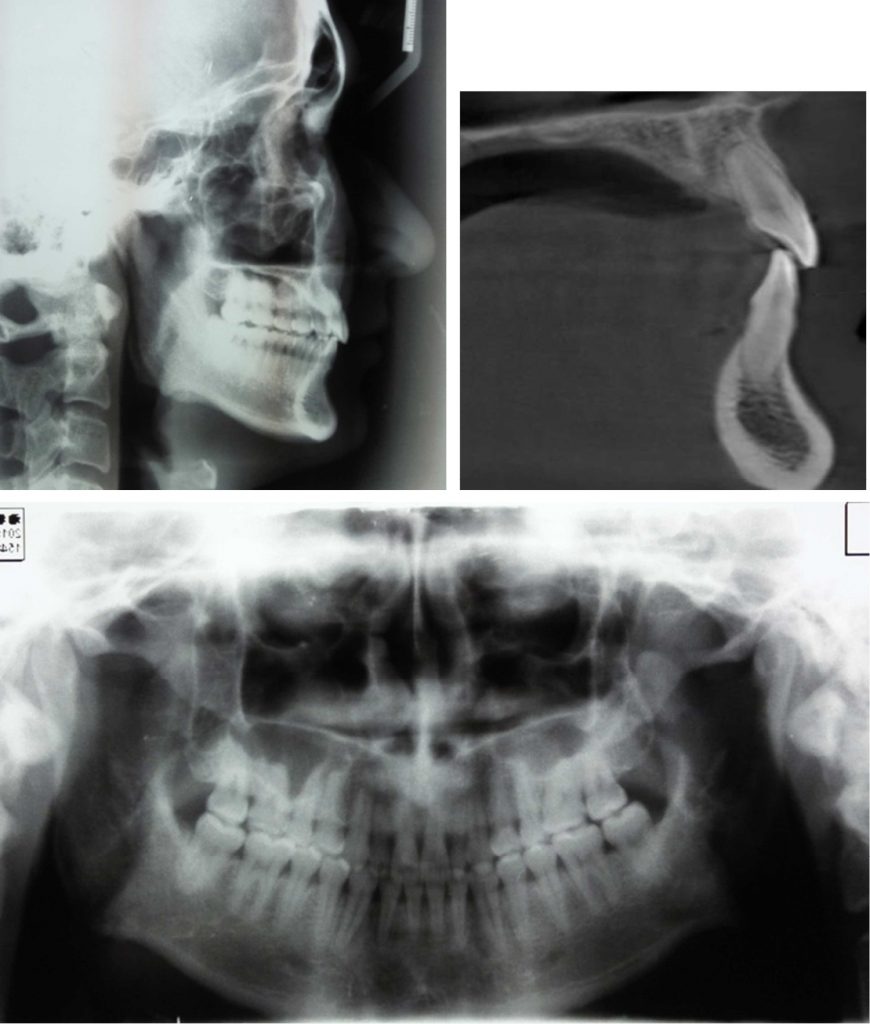

Streszczenie: W pracy opisano zmodyfikowany aparat Nance’a (modified Nance appliance, MNA) jako opcję leczenia dorosłego pacjenta z klasą II podtypu 2 (CII/2), ze zgryzem głębokim, z dojęzykowym nachyleniem górnych siekaczy i dehiscencją powierzchni twarzowej wyrostka zębodołowego nad korzeniem jednego z nich, zidentyfikowaną za pomocą tomografii stożkowej (CBCT). Przedstawiono wskazania do zastosowania MNA, a także krótki opis konstrukcji aparatu oraz biomechaniczną analizę efektów leczenia. Osiągnięto pełną intruzję i uzyskano kontrolę korzeni bez powiększenia ubytku kostnego. Wyniki leczenia były satysfakcjonujące.

Leczenie ubytków kostnych wyrostka zębodołowego, tj. dehiscencji i fenestracji, u pacjentów ortodontycznych pozostaje trudnym zadaniem. Dehiscencja objawia się brakiem fragmentu blaszki policzkowej lub językowej wyrostka zębodołowego, z tendencją do odsłonięcia powierzchni korzenia i zajmowania brzeżnego odcinka kości [1]. Dehiscencję stwierdza się często przed leczeniem ortodontycznym w okolicy spojenia żuchwy, szczególnie u pacjentów dorosłych [2]. Aby uniknąć dodatkowego ryzyka, przed rozpoczęciem leczenia ortodontycznego należy ocenić anatomię wyrostka zębodołowego. Idealną opcją obrazowania w takiej sytuacji klinicznej jest obecnie [...]